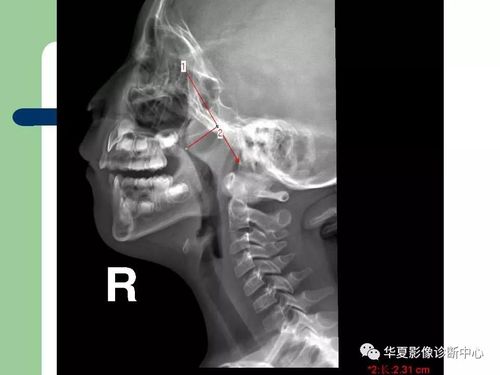

腺样体肥大的x线诊断

如何判断腺样体肥大

腺样体肥大ct图详解

腺样体肥大ct测量图片